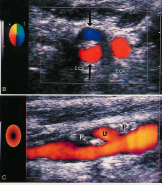

what is are these images demonstrating?

atherosclerotic plaque early stage (Traditionally sonographically we don’t see any changes until step 3, fibrous plaque. Studies have shown intima- medial thickness measurements can “predict” further plaque development. With changes in life style and medication to slow process)

identify what type of plaque

what are their characteristics?

all Heterogeneous - mixed echoic pattern. Homogeneous is- uniform plaque texture

what type of plaqe is shown here?

smooth plaque

what type of plaque is this

irregular, complex. older, has been there longer b/c hyperechoic